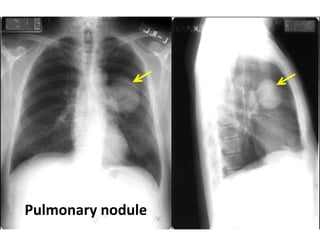

Pulmonary nodules

Pulmonary nodule